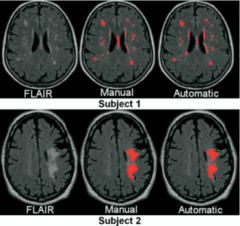

Results from the new implementation are:

One WML Segmentation side:

- Skull stripping is being developed. For WML segmentation, skull stripping is not THE most critical piece. The accuracy requirement is relaxed.

- Support vector machine classification will be using/extending SVMShapeAnalysis in Namic Sandbox developed by MIT group.

- Zhiqiang Lao, Dinggang Shen, Dengfeng Liu, Abbas F Jawad, Elias R Melhem, Lenore J Launer, Nick R Bryan, Christos Davatzikos, Computer-Assisted Segmentation of White Matter Lesions in 3D MR images, Using Pattern Recognition, Academic Radiology, 15(3):300-313, March 2008.